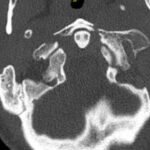

The Jefferson fracture classification system describes fractures of the atlas (first cervical vertebra or C1). Jefferson fractures with potential tears in the transverse ligament can cause cervical spine instability and can result in neurologic injury if not appropriately diagnosed and managed. We present the case of a 54-year-old man who fell head first with cervical spine tenderness and upper extremity paresthesias. The patient’s Jefferson fracture was diagnosed via computed tomography. The patient was then treated non-operatively for his Jefferson fracture, and he had an unremarkable hospitalization. Emergency physicians should obtain surgical consultation and consider the possibility of ligamentous injury in patients suffering injury to the cervical spine.